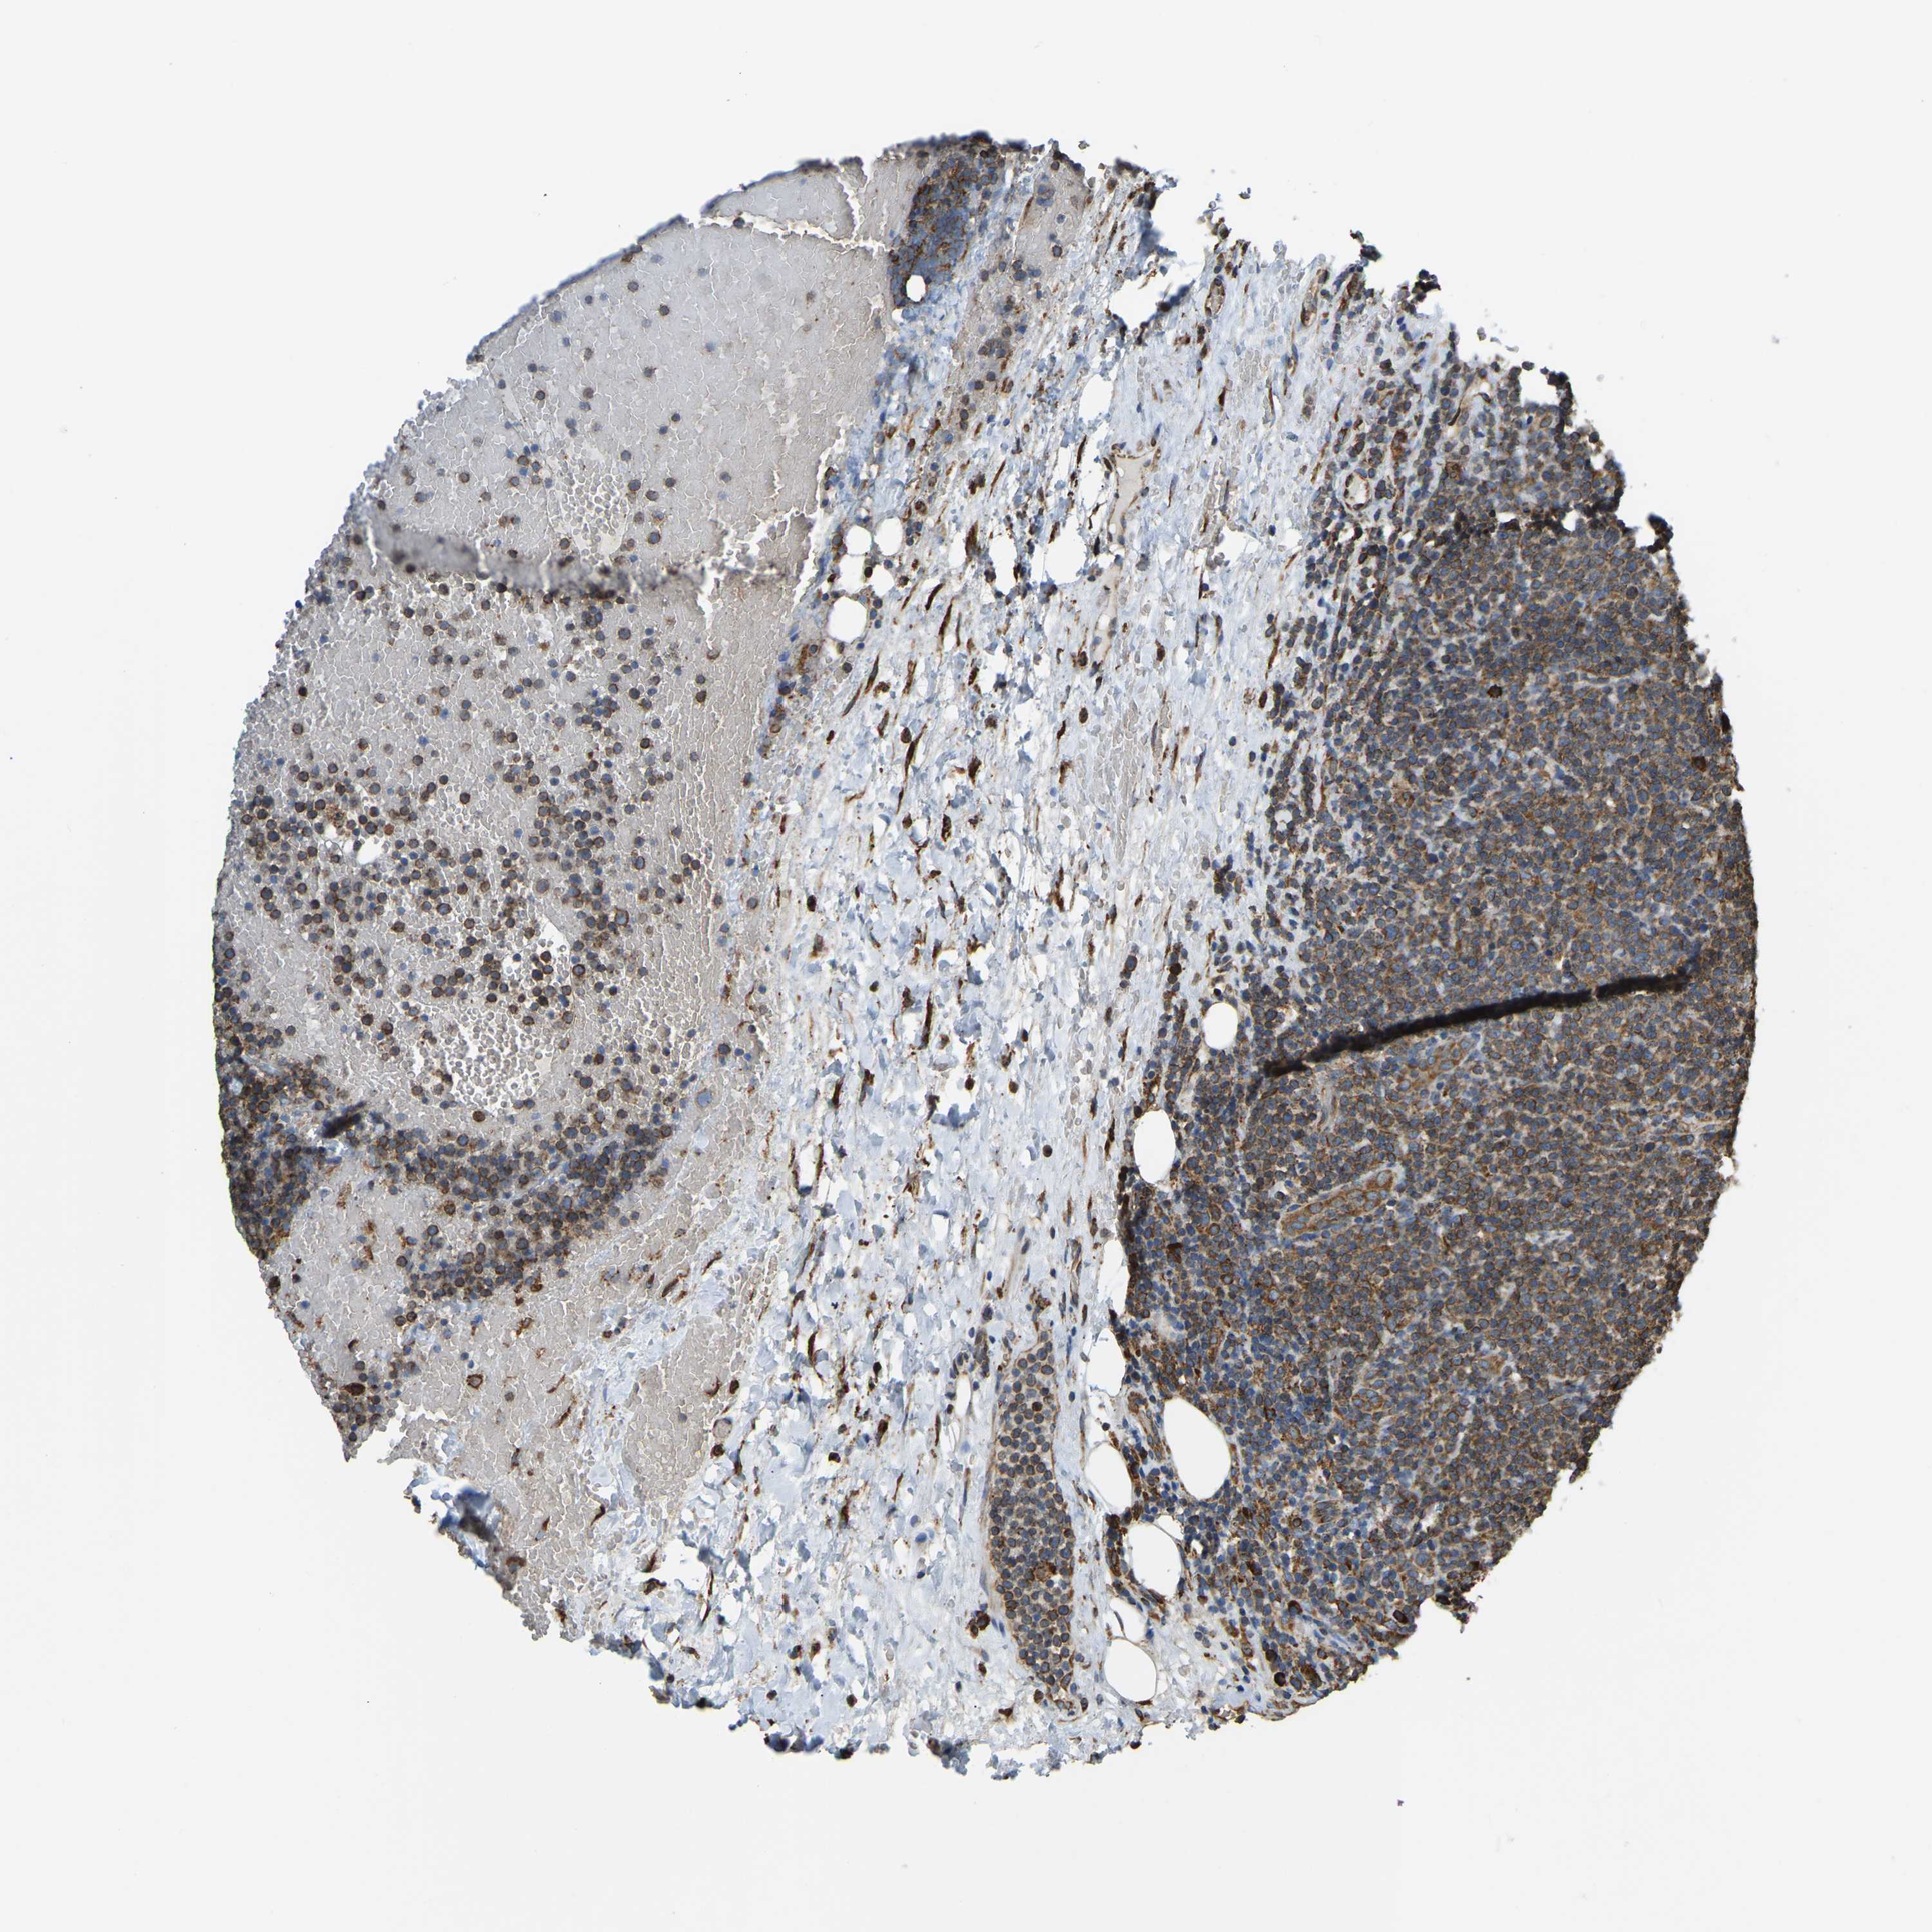

CANCER LYMPHOMA Show tissue menu

LYMPHOMA - Protein expressioni

A mouse-over function shows sample information and annotation data. Click on an image to view it in a full screen mode. Samples can be filtered based on level of antibody staining by selecting one or several of the following categories: high, medium, low and not detected. The assay and annotation is described here.

Each image is clickable and will lead to virtual microscopy that enables deeper exploration of all samples and also displays staining intensity scores, fraction scores and subcellular localization as well as patient and tissue information for each sample.

Antibody HPA019130

Staining

High

Medium

Low

Not detected

Intensity

Strong

Moderate

Weak

Negative

Quantity

>75%

75%-25%

<25%

None

Location

Nuclear

Cytoplasmic/membranous

Cytoplasmic/membranous,nuclear

Hodgkin's disease, NOS

Malignant lymphoma, non-Hodgkin's type, High grade

Malignant lymphoma, non-Hodgkin's type, Low grade